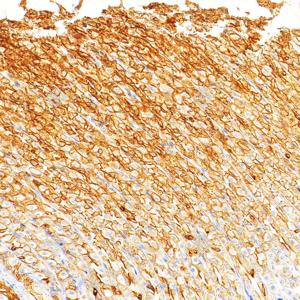

IHC检测Cytokeratin 18蛋白(货号 GB15232). 样品: 人肺癌, 4%多聚甲醛 (货号G1101) 固定12-24小时. 抗原修复: 柠檬酸抗原修复液(干粉, pH 6.0) (G1201), 高压锅均匀喷气计时2分钟. —抗: 1: 500稀释, 4℃ 孵育过夜. 二抗: S-vision免疫组化多聚二抗(山羊抗小鼠), 即用型(货号G1301), 室温孵育20分钟. |